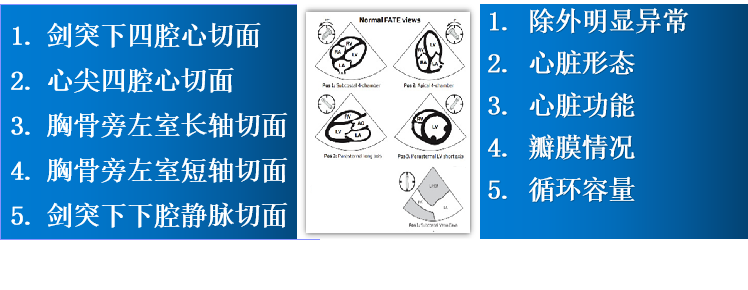

重症心脏超声- FATE方案:

是重症病人循环管理推荐的目标导向超声评估评估方案之一,在此基础上扩展快速的下腔静脉超声检查,增加和完善容量状态和液体反应性的评估。

胸骨旁左心室长轴切面

剑突下四腔心切面

心尖四腔切面

剑突下下腔静脉切面